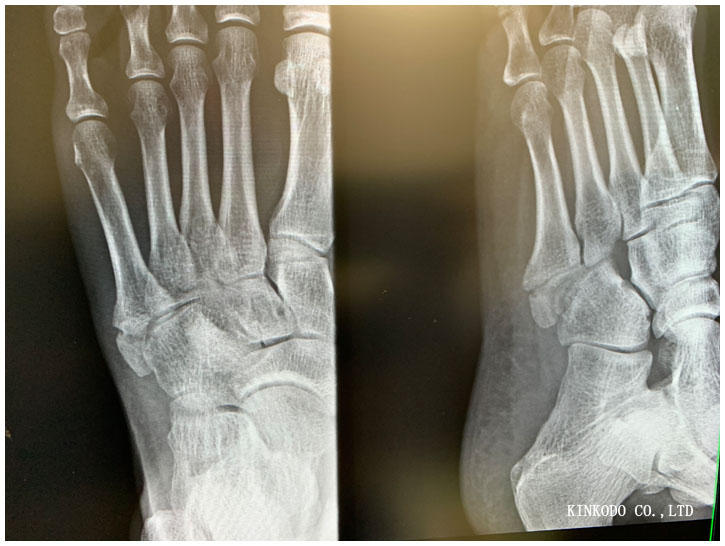

診察室に入ると既にレントゲン写真が先生の机の横にあり。先生来る前にスマホで。

どう変わっているのか?変わっていないのか?

まだなのか?どうなのか?

先生の説明によるとまだ骨折線は見えている。完全にくっつくにはまだ日にちがかかる。

と言われてももう走っているので、正直に先日400メートル×15本インターバルやってますけどと伝えました。

1月30日だったよね!(大阪ハーフ)と言われて、それでは安心の為にもその前にもう一度レントゲン撮っておくか?と言われて再度受診することになりました。

まだ完治じゃないのか・・・まあ走るけど。